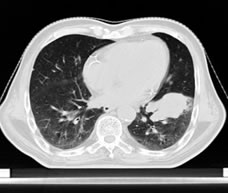

左肺下叶肺癌

放疗前放疗后